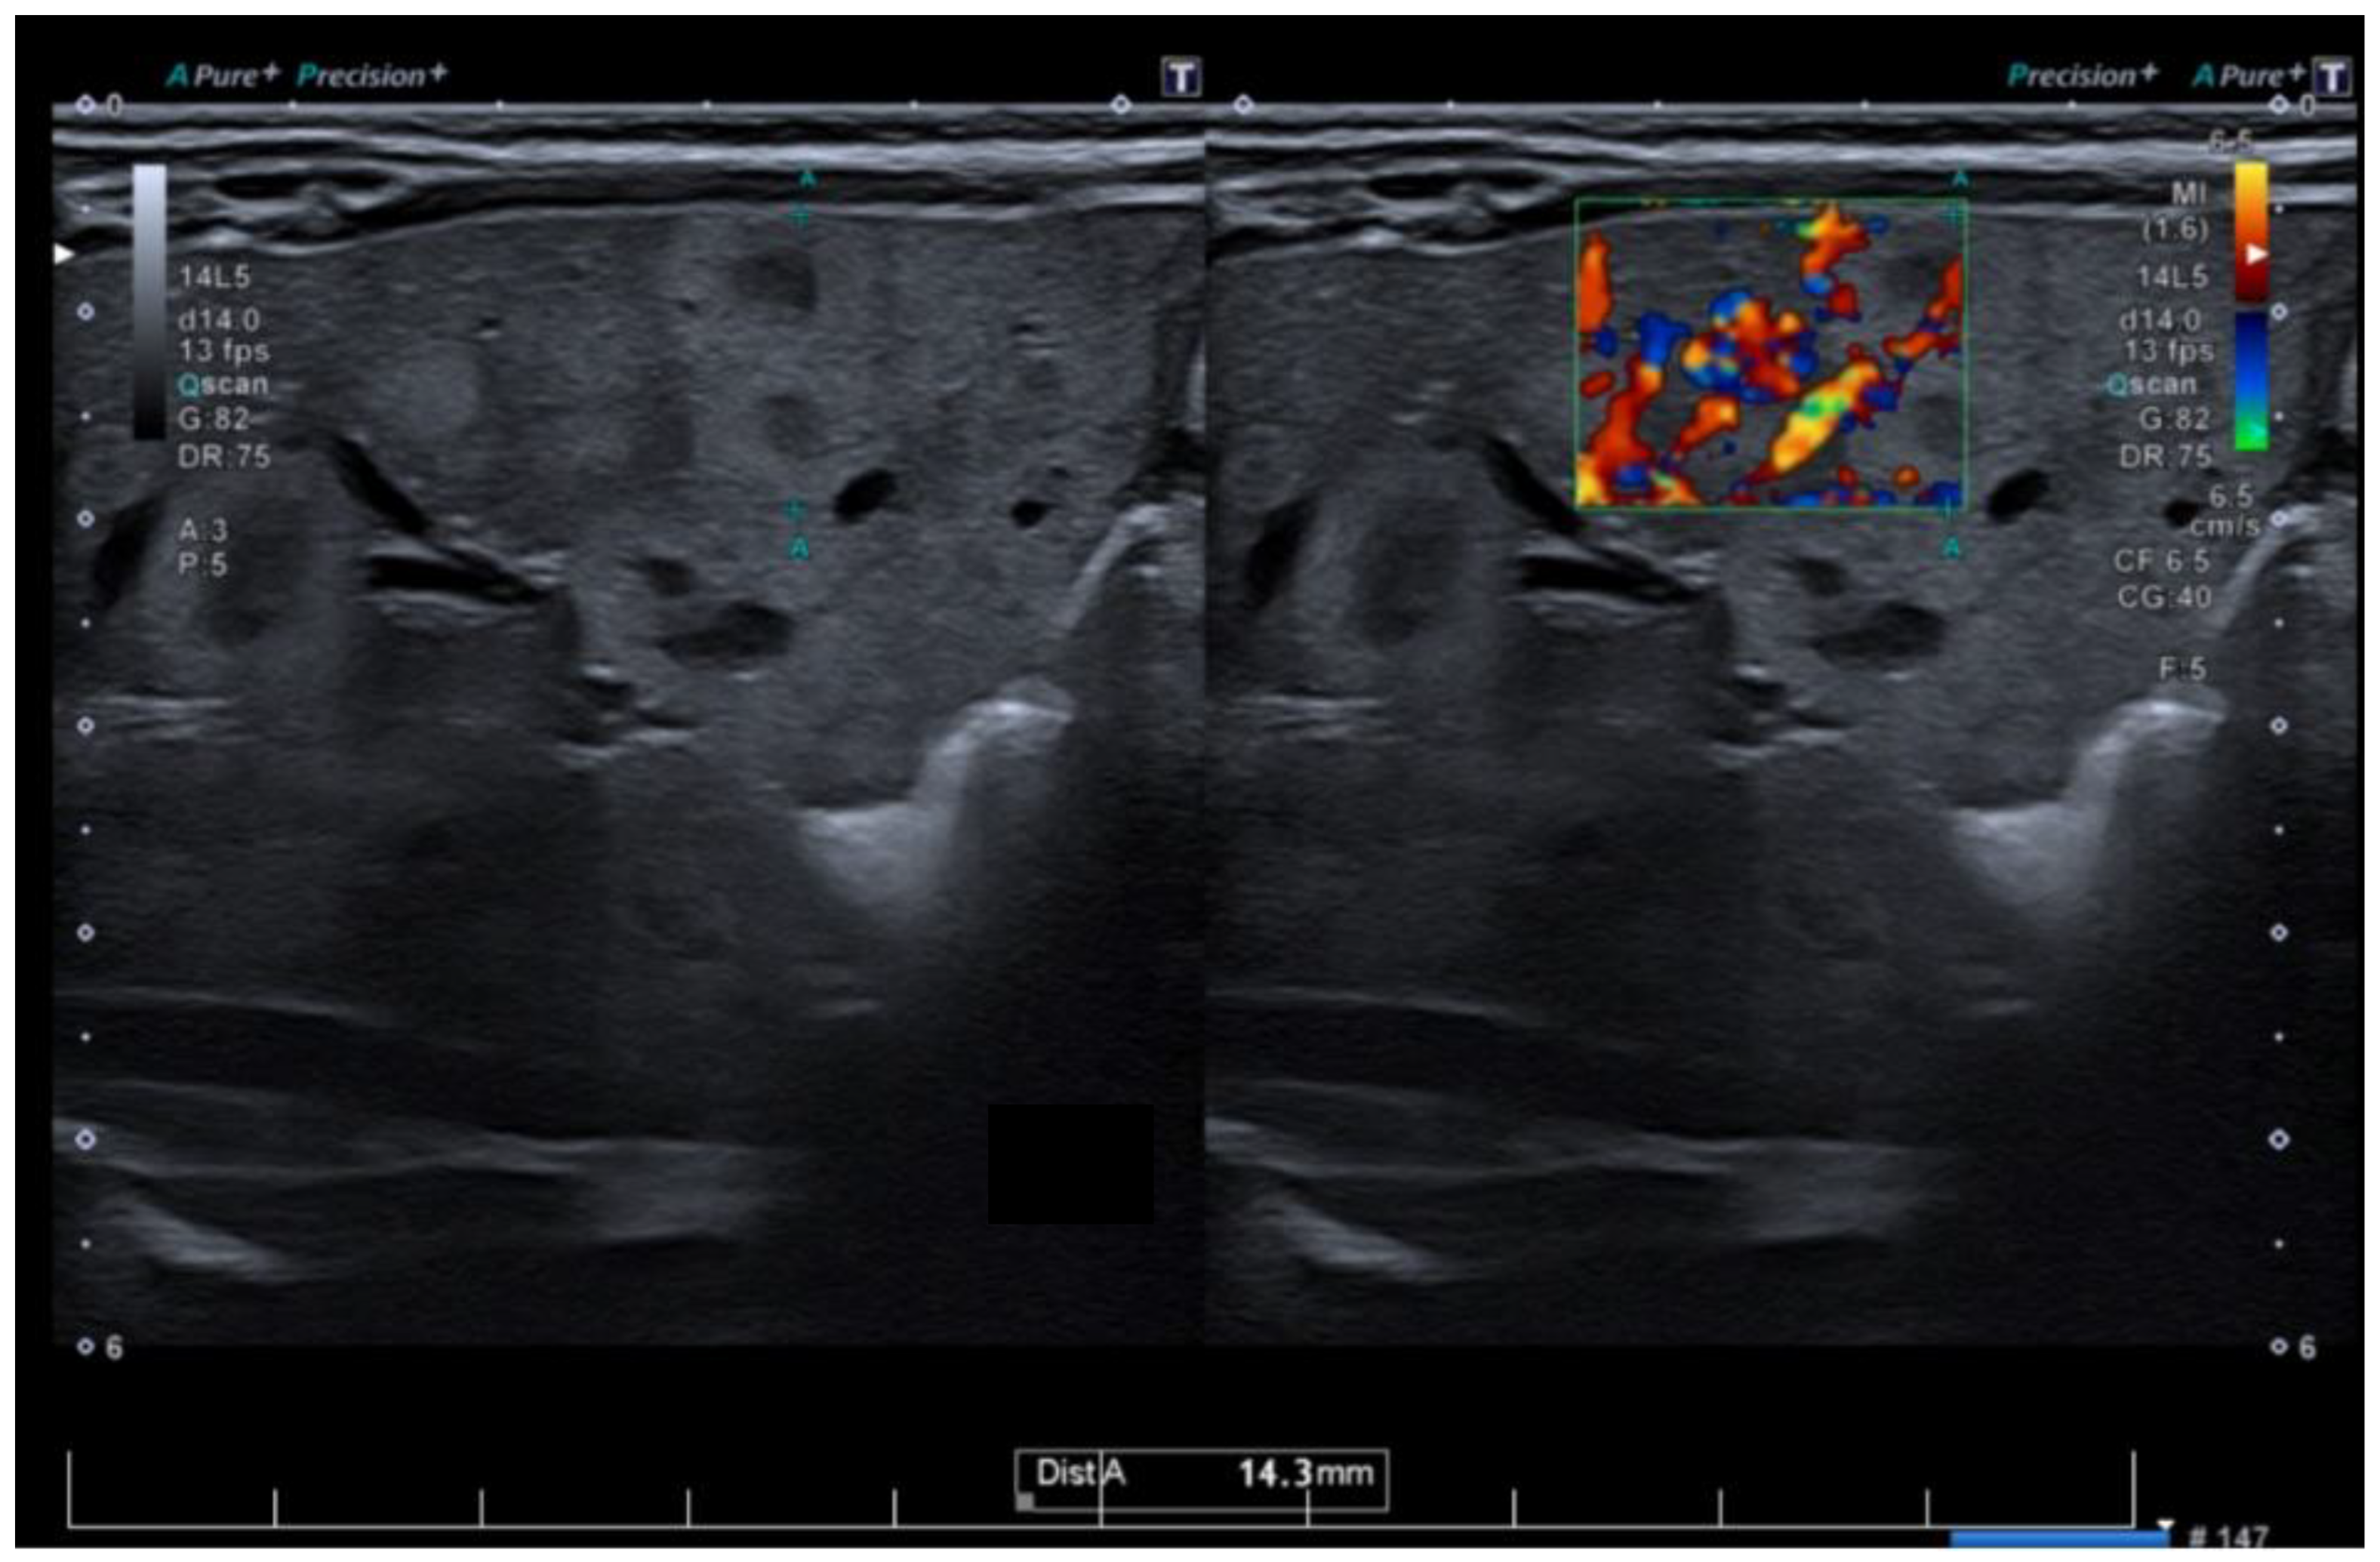

The patient was admitted to our service at two weeks of life for further evaluation. The physical examination revealed disseminated hemangiomas and subtle jaundice. Given the extensive cutaneous and mucosal hemangiomas, as illustrated in Figure 1, an abdominal ultrasound was performed. The examination revealed multiple hepatic hemangiomas (Figure 2), the largest of which measured 25 mm. Additionally, there was evidence of mild dilation and distortion of the hepatic veins, along with an enlarged hepatic artery measuring up to 4 mm. Two vascular lesions were also identified in the spleen. Doppler ultrasound showed no signs of arteriovenous shunting. Furthermore, cranial ultrasound revealed subependymal and frontal horn cysts, considered to be sequelae of a probable antenatal intraventricular hemorrhage.

In most cases, diagnosis relies predominantly on clinical evaluation and patient history. If the diagnosis is inconclusive, if more than five lesions are present, and when an extracutaneous involvement is suspected, a comprehensive diagnostic workup should include imaging studies, with a focus on abdominal ultrasonography (US), which reveals a well-defined mass. Infantile hepatic hemangiomas are generally characterized by low or even absent intralesional Doppler signal, consistent with their slow circulation [2,3]. Increased vascularity is more commonly observed in the feeding and draining vessels surrounding the lesion, rather than within the lesion parenchyma. This distinction is clinically relevant, as it helps differentiate infantile hemangiomas from vascular malformations, particularly arteriovenous malformations, which are true high-flow entities [4]. In cases with suspected multi-organ involvement or inconclusive findings, advanced imaging techniques such as magnetic resonance imaging (MRI) or computer tomography scans (CT) may be necessary to assess the extent of visceral disease [12,13]. Histopathological confirmation using the endothelial marker GLUT-1 immunostaining is a highly sensitive and specific diagnostic tool for infantile hemangiomas. Nevertheless, liver biopsy is infrequently required in routine clinical practice and should not be performed routinely. Indications for biopsy extend beyond suspicion of malignancy and include situations such as atypical imaging findings, uncertain diagnosis, or inadequate response to standard therapy. Recently, electronic colorimeters—widely accessible on computers and mobile devices—have been increasingly used to help differentiate IHs from other vascular tumors and malformations by providing objective color analysis [2,14]. Laboratory testing plays a crucial role in assessing and monitoring MIH. Basic blood tests should include a complete blood count (to evaluate for anemia or thrombocytopenia), liver function tests (to determine the hepatic involvement and potential dysfunction), and coagulation studies. In the present case, cholestasis is primarily attributed to extrinsic compression of the intrahepatic biliary ducts by multiple hepatic hemangiomas, leading to impaired bile flow.

Figure 2. Hepatic ultrasonography with color Doppler demonstrates multiple hypoechoic lesions consistent with hepatic hemangiomas, showing internal vascular flow.